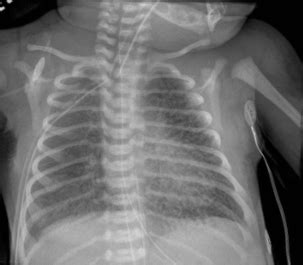

How PIE Appears on Chest X-rays

Okay, let’s get down to the nitty-gritty of how pulmonary interstitial emphysema radiology actually looks on a chest X-ray . This is often the first line of imaging used. When a radiologist looks at an X-ray of a patient with PIE, they’re scanning for specific patterns. One of the classic signs is the appearance of linear lucencies, which are essentially dark lines on the X-ray film. These lines represent air tracking within the interstitial tissues. Imagine tiny air bubbles or streaks running through the lung tissue, separate from the normal branching pattern of airways and blood vessels. Another key finding can be a ‘cystic’ or ‘bubble-like’ appearance, where larger pockets of air have accumulated in the interstitial space, sometimes looking like clusters of small balloons. You might also see signs of lung hyperinflation, where the lungs appear larger than normal, often because air is getting trapped. Sometimes, PIE can lead to a condition called pneumothorax, which is air in the space outside the lung, between the lung and the chest wall. This is a serious complication and appears as a dark space separating the lung from the chest wall on the X-ray. The diaphragm might also appear flattened due to the hyperinflation. It’s important to note that PIE can sometimes be subtle on an X-ray, especially in its early stages or if it’s mild. The radiologist has to be really vigilant and compare the current X-ray with previous ones if available to spot any changes. They’re looking for deviations from the normal, healthy lung pattern, and PIE creates a very distinct set of deviations. It’s a diagnostic puzzle, and the X-ray provides the primary pieces to solve it. The clarity and detail needed to spot these subtle linear lucencies and cystic changes are what make the radiologist’s expertise so vital in interpreting these seemingly simple images.